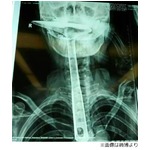

フライ返し飲み込み命の危機に、意味が分からず家族や医師は困惑。